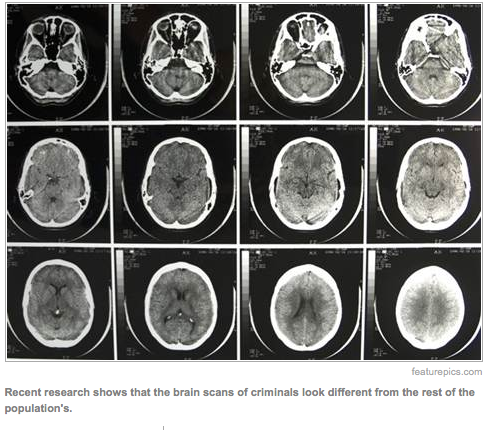

They are doing cutting-edge research into understanding Alzheimer’s diseases, multiple sclerosis, traumatic brain injury and post-traumatic stress disorder amongst combat veterans. They are also trying to find the causes and treatments for psychiatric diseases such as bipolar disorder, depression and schizophrenia. Brain imaging techniques allow scientists to see differences in brains between healthy people and those with mental illnesses. These techniques may help map out the mysteries of why people get depressed, become manic, hear voices and see things that aren’t there. And, why people commit crimes and do evil things.

As his case moves through the legal system, and he likely tries for an insanity defense, his mental state will become the subject of study and debate by legal experts and forensic psychiatrists. Perhaps neuroscientists will scan his brain, and they’ll be able to develop a picture of where things started to go wrong with him.